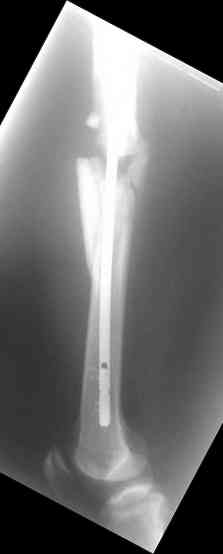

Надеюсь сейчас показать перелом, а потом синтез.